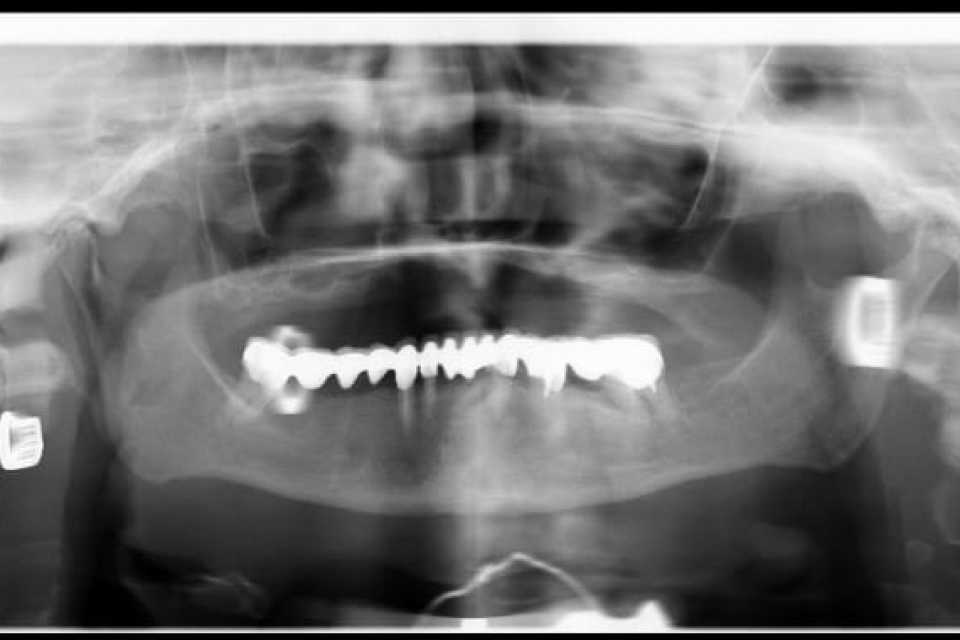

Pacienta, în vârstă de 75 de ani, veche purtătoare de proteza totală maxilară, trecută prin 2 adiții osoase și implanturi nereușite, se prezintă în cadrul clinicii cu dorința găsirii unei soluții de reabilitare protetice fixe a maxilarului.

Împreună cu pacienta am optat pentru implanturi orale speciale,o ultima soluție pentru pacienții cu atrofie osoasă severă.

Sub anestezie generală s-au inserat 4 implanturi zigomatice și 2 implanturi pterigoide și 1 implant dentar normal cu ajutorul cărora am realizat o lucrare dentară protetică fixă din ceramica pe zirconiu insurubabila de 14 elemente.